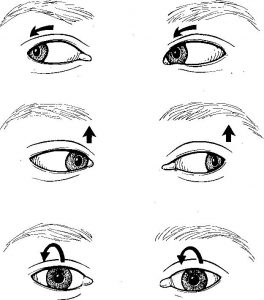

Ruim 12 uur onderweg geweest en 578 kilometers gereden (Leeuwarden-Antwerpen vv) zijn wij (mijn vrouw en ik) blij maar wel moe dat we dit bezoek aan professor dr. Floris Wuyts werkzaam aan het UZA te Antwerpen hebben volbracht. Het heeft mij in ieder geval een nieuwe diagnose opgeleverd nl. Vestibulaire Paroxysmien (VP).Na een intake gesprek met NKO arts Van Haesendonck-Gilles en professor Wuyts, heb ik mijn verzamelde medische gegevens, een gedetailleerde overzicht van de evenwichtsstoornissen vanaf 2012 tot heden en een ingevulde SO STONED formulier ter beschikking gesteld, zodat er een grote hoeveelheid gegevens aanwezig was omtrent mijn ziekteverloop. Vervolgens heb ik nog een uitgebreide gehoortest gedaan en tenslotte kreeg ik een bril op waardoor Floris mijn oog bewegingen kon zien door mij in een verschillende houdingen te plaatsen. Als er een vorm van duizeligheid of misselijk gevoel optreedt is het zichtbaar op het scherm (zie foto’s).

Bij de foto’s: Professor dr. Floris Wuyts onderzoekt mij en kijkt naar de oogbewegingen op het scherm.

Op maandag 27 juni om 7:55 uur werd ik binnengeroepen in de behandelkamer van het MCL te Leeuwarden voor het ENG onderzoek (Elektro Nystagmo Grafie). De begeleidende verpleegkundige legde in duidelijke en begrijpelijke taal steeds uit wat er ging gebeuren en wat mogelijk het gevolg zou kunnen zijn. Het was voor mij de vierde keer en toch was dit weer anders. Je krijgt een zware helm op je neus gedrukt met een afsluitbaar venster. In het bovenste gedeelte van de helm zit een camera die de oog bewegingen registreert. Bij alle acties moet je de ogen goed open houden. Op een scherm waar je naar kijkt beweegt een wit puntje die je moet volgen. Steeds iets anders en sneller. Daarna rollen er zwart/witte banen over het scherm die steeds in tempo versnellen. Het is de bedoeling dat je dan recht vooruit blijft kijken.

Op maandag 27 juni om 7:55 uur werd ik binnengeroepen in de behandelkamer van het MCL te Leeuwarden voor het ENG onderzoek (Elektro Nystagmo Grafie). De begeleidende verpleegkundige legde in duidelijke en begrijpelijke taal steeds uit wat er ging gebeuren en wat mogelijk het gevolg zou kunnen zijn. Het was voor mij de vierde keer en toch was dit weer anders. Je krijgt een zware helm op je neus gedrukt met een afsluitbaar venster. In het bovenste gedeelte van de helm zit een camera die de oog bewegingen registreert. Bij alle acties moet je de ogen goed open houden. Op een scherm waar je naar kijkt beweegt een wit puntje die je moet volgen. Steeds iets anders en sneller. Daarna rollen er zwart/witte banen over het scherm die steeds in tempo versnellen. Het is de bedoeling dat je dan recht vooruit blijft kijken.Het onderzoek vervolgde met het achterover vallen en draaien met het hoofd. Eerst naar links en daarna na rechts. Vervolgens liggend snel naar links en dan naar rechts draaien en blijven liggen. Dan hetzelfde maar dan andersom.

Nu de Epley manoeuvre niet heeft geholpen is plan B uit de kast gehaald. Die richt zich op mijn aandoening Recurrent Vestibulopathy. Ik doe nu gewenningsoefeningen onder leiding van fysiotherapeute Marije van der Werf (Axon fysiotherapie Deinum), die gespecialiseerd is in het behandelen van patiënten met een evenwichtsstoornis. De eerste serie van zeven oefeningen die gebaseerd zijn op oogbewegingen heb ik nu gedaan. Het was in begin wel even wennen om de diverse prikkels die het veroorzaakte te verwerken. Van een aantal oefeningen merkte ik niets. Op het lijstje staan 28 oefeningen (Cawthorne & Cooksey), dus ben er nog niet klaar mee.

Vanmiddag bij Axon Fysiotherapie in Deinum geweest voor een intakegesprek en een uitleg gekregen over de oefeningen (Cawthorne & Cooksey) die ik moet doen. Het zijn zogenaamde gewenningsoefeningen om het gevoel van het evenwicht weer terug te krijgen. Vooral ook op die plekken waar de balans zoek is.Bij de eerste oefening, hoofd stil en de ogen laten bewegen naar boven en naar beneden en weer terug, ging het redelijk maar gaf toch enkele prikkels af.

De tweede oefening ging minder en ben gestopt na een paar keer te hebben uitgevoerd. Ik kreeg een raar gevoel in mijn hoofd en werd misselijk. Ik moest mijn arm strekken en met de vinger omhoog van links naar rechts bewegen. Hoofd stil en de vinger volgen met de ogen.

In eerste instantie de eerste oefening gaan doen de komende week. Kijken of dit op den duur wel goed gaat. Vier keer per dag 15 oogbewegingen op en neer.

1. Cawthorne & Cooksey oefeningen

De oefentherapie volgens Cawthorne & Cooksey is gericht op het verminderen van duizeligheidklachten en verbeteren van het evenwicht. De oefeningen bestaan uit oog-, hoofd- en lichaamsbewegingen die bedoeld zijn om de duizeligheid te provoceren. Hiermee wordt het herstel van het evenwichtsgevoel in de hersenen versneld.